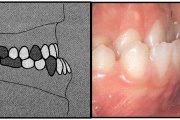

Koonilise kujuga lisahammas ülemiste tsentraalsete lõikehammaste vahel.

Suulaepoolt lõikunud koonilise kujuga lisahammas